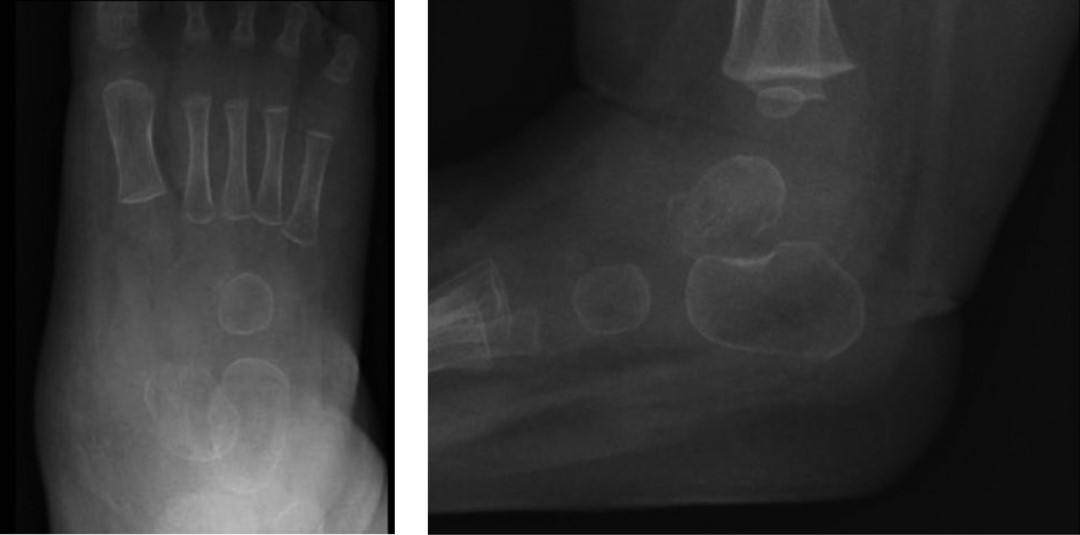

Figura 5